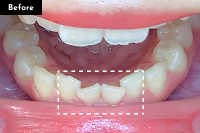

Basicプラン

上下前歯12本の部分矯正

20代 女性

治療費用:Basic 33万円(税込)

治療期間:4ヶ月

- Before

After